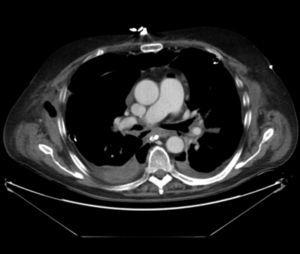

Pulmonary vein obstruction is usually an early complication, occurring during the first few hours after transplantation, and causes severe symptoms. Marked hypoxia, pulmonary edema, and pulmonary infiltrates are observed. If the lower lobe is more severely affected, a high suspicion for such a complication is warranted, and an early additional diagnostic test should be ordered. The initial test should be a transthoracic or transesophageal echocardiogram, in spite of this test being only useful for diagnosis when performed by an experienced operator, due to a challenging visualization and interpretation after recent surgery 6. Alternatively, chest CT angiography can be used, which also allows artery suture and distal vascularization to be assessed and reconstructions to be produced. CT angiography establishes the diagnosis in most cases. Anticoagulation using heparin and clinical course monitoring is used to manage partial thromboses and stenoses. In the event of a complete vein obstruction or a poor course, in patients with a very recent surgery, re-transplantation or lobectomy for double-lung transplantations, may be needed. If the patient is in a stable condition, several days have elapsed, and anatomic characteristics are favorable, an angioplasty with dilation and stent implant can be considered.

Figure 3. Coronal view in CT angiography showing complete lower pulmonary vein obstruction after left lung transplantation.

Figure 4. CT image showing extensive lung infiltrates in lower left lobe resulting from lower pulmonary vein obstruction.